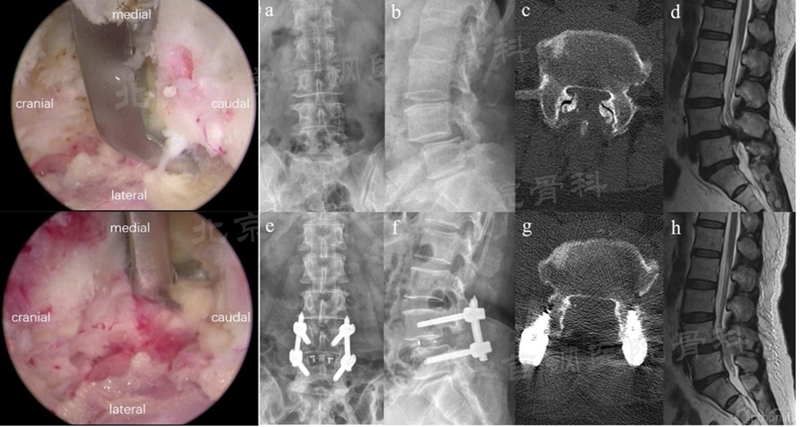

(5)双侧双cage融合术的入路

双通道脊柱内镜下双侧双cage融合术最早由我国学者张伟教授提出,直到上月末才以论文形式正式发表出来[8]。该技术同侧处理和植入cage基本与BE-TLIF相同,但借助对侧Zhang切口实施对侧减压、椎间隙处理和对侧cage植入(如图22),以增加对侧融合率和减压效率,对于滑脱松解复位也具有很强的优势。同时,该技术也是Zhang切口应用的重要拓展,具有一定的应用前景。

图22 双侧双cage融合术的对侧操作入路和镜下视野(图片来源于文献)

(5)双侧双cage融合术:该术式除了植入双cage的优势外,还可以借助Zhang切口对对侧进行高效率的减压,同时可以切除对侧关节突关节以实现滑脱更好的复位(如图26)。

图26 利用Zhang切口可以高效处理对侧减压,切除对侧小关节实现滑脱复位(图片来源于文献)